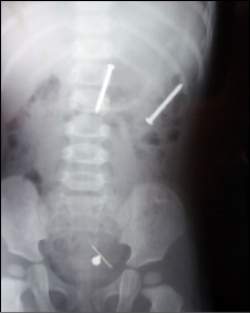

Radiografias confirmaram a presença de pregos e alfinetes no estômago da criança.